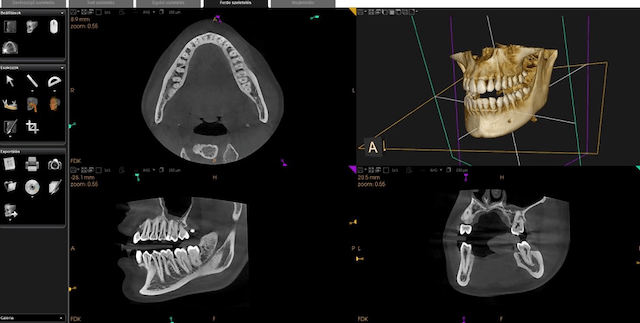

A hagyományos 2D panoráma röntgenfelvétel nem nyújt elegendő információt az orvos számára egy műtét megtervezéséhez és végrehajtásához. A 2D felvétellel ellentétben a 3D-s felvételek pontos diagnózis felállítását teszik lehetővé kizárva a kétségeket és találgatásokat. A CBCT magas felbontású, részletes képet ad az állcsontok formájáról, melynek köszönhetően a fogászati beavatkozások hatékonyságát maximalizálni, a kezelési időt minimalizálni tudjuk.

Az implantáció pontos tervezést igényel, amely során az orvos felméri a páciens csont mennyiségét, azok anatómiai elhelyezkedését, azért, hogy az implantátumokat a legideálisabb pozícióba tudja behelyezni. Ennek a folyamatnak elengedhetetlen feltétele a 3D felvétel.

A 3Ds felvétel nem csak az orvost segíti a munkájában, hanem a páciens számára is könnyen láthatóvá, érthetővé és elfogadhatóvá teszi a szükséges kezelési tervet. Nagy előnye a Cone Beam CT-nek a hagyományos CT-vel szemben, hogy sugárterhelése lényegesen alacsonyabb.

A 3D CBCT felvétel segít feltérképezni az eltávolításra és pótlásra szánt fogakat. Pontosan meghatározza más létfontosságú struktúrák elhelyezkedését és térbeli formáját, mint például az alsó állcsontot ellátó idegek, erek és az arcüreg. Ezen kritikus struktúrák mindegyikének megkeresése, elemzése és értékelése a különbség a sikertelen és a sikeres műtét között.

A CT felvétel különösen kritikus szerepet játszik annak meghatározásában, hogy a páciens rendelkezik-e megfelelő mennyiségű és minőségű csonttal, amelybe az implantátum behelyezhető.

Az állcsont egy háromdimenziós szerkezet, különböző magasságú-, szélességű- és hosszúságú területekkel. Az egyszerű kétdimenziós röntgenfelvételek nem adnak elegendő információt a különböző anatómiai tulajdonsággal rendelkező páciensek egyedi állkapocs struktúrájáról, csontuk mennyiségéről, minőségéről és a potenciálisan gyenge területekről.